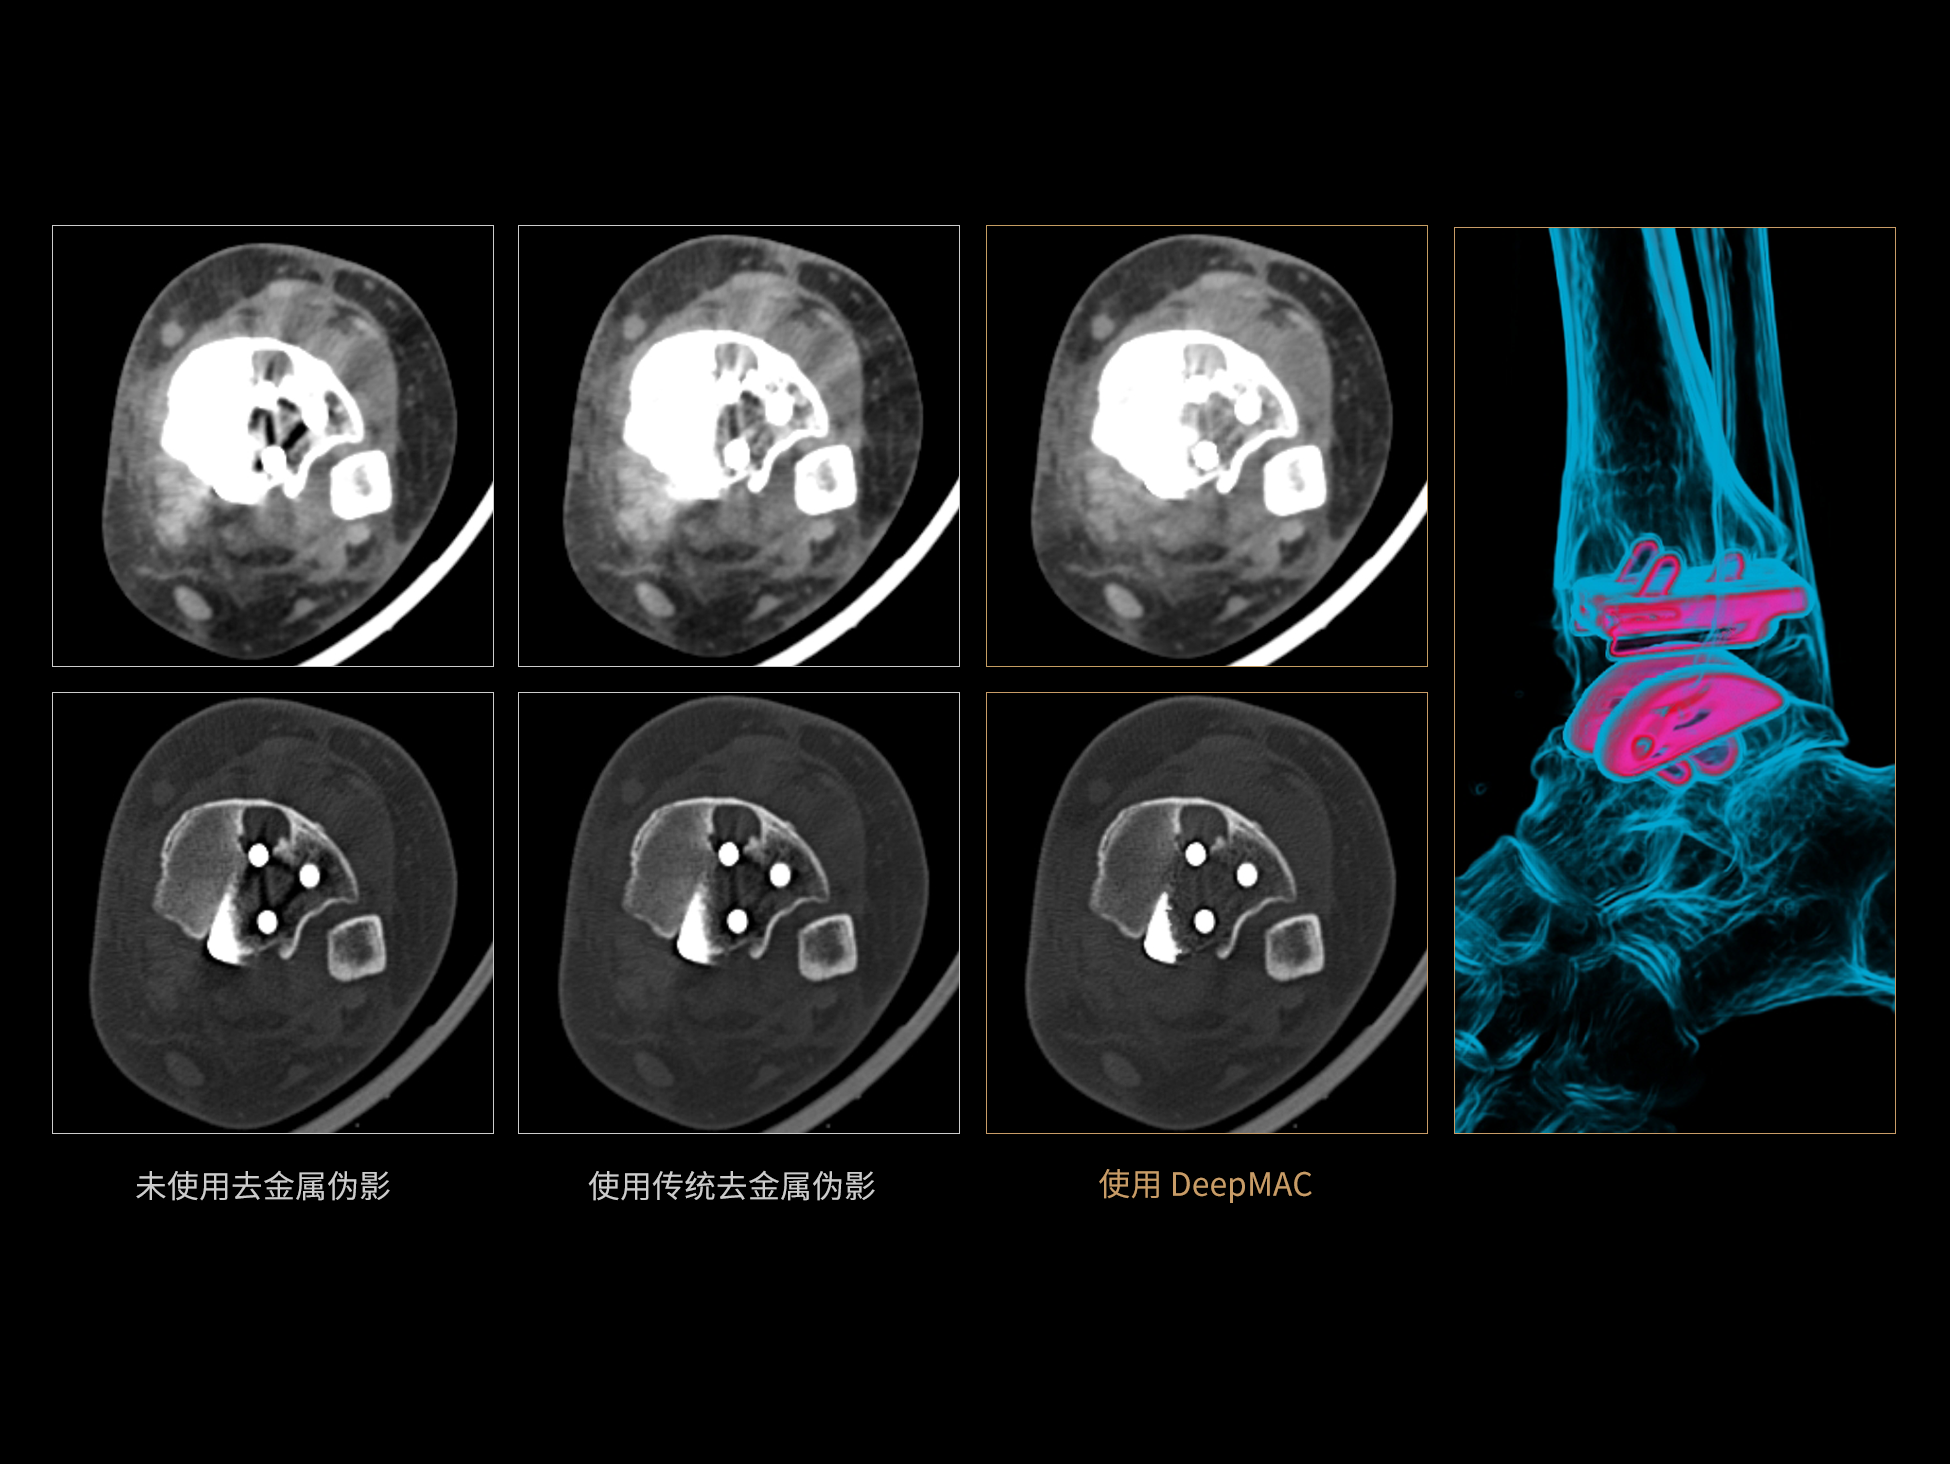

uCT 868 搭载联影最新一代 uSense 人工智能平台,将智能化深度融入 CT 扫描全流程,从感知细微生理运动到精细结构探测,再到多场景诊疗优化。以 AI 为核心驱动力,uSense 重塑成像各环节,打造高效、高清的智慧扫查体验。在心脏成像领域,uSense 结合宽体探测器、心脏专研AI重建算法与AI冠脉运动追焦技术,在保持低剂量的同时,有效抑制运动伪影,精准呈现软斑块、混合型斑块及支架细节,助力冠脉成像惠及更多患者。针对多科室疾病临床应用场景,uSense 平台提供全方位的智能解决方案:包括头部运动伪影智能校正、金属植入物伪影抑制、扫描视野扩展等先进算法。这些创新技术使 uCT 868 能够构建覆盖全场景的智能诊疗体系,持续拓展 AI 赋能医学影像的边界。